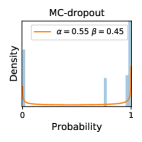

To model how different classifiers will respond to a given input , we assume that the prediction from classifier is sampled from a beta distribution that is characterized by two parameters by and . We further assume that is fixed to the same constant value for all ’s. Under this assumption, each input can be described by ( can be calculated since is fixed), easing further analysis. The Severity Level (SL) of the case represented by image can be characterized by the parameter . The larger the value of , the more severe the case of is. When and are close, the case is ambiguous as the distribution shifts towards being symmetric (i.e. signifying much disagreement among classifiers) rather than being one-sided (i.e. consensus among classifiers that is negative or positive). We provide a set of examples in Figure 2 and also Figure S.8 in the supplementary materials showing how the beta distribution can be used to capture diverse predictions given by an ensemble learner.

In contrast, the MC-dropout method showed the worst overall performance among the three, as it can be seen from the high ratios of SL0 examples among the uncertain negatives in Figure 4. The histograms in Figure 2 provides another perspective to look into the phenomenon, where a decent proportion of MC-dropout model’s predictions on SL0 inputs entailed low confidence (far from 0 or 1), which from another angle explained why MC-dropout was less specific in terms of lower FNP; many no-DR inputs (i.e. SL0) were erroneously assigned high uncertainty by MC-dropout models.

It is still an open question why the evaluated MC-dropout networks signaled relatively high uncertainty on SL0 & SL3 & SL4 data that are less likely to be ambiguous. We conjecture that much of the “uncertainty” indicated by disagreement among test-time dropout samples actually reflects the stochastic nature of dropout networks rather than the real decision uncertainty associated with the data. It is worth noting that the MC-dropout model we evaluated was not weak per se; they all achieved above Area Under Curve (AUC) scores on test sets. The weakness of individual test-time samples (which explains their low-confidence predictions on SL0 & SL3 & SL4) might have been hidden when they are aggregated into an ensemble—a well-known advantage of ensemble learning. Our results suggested that the uncertainty information given by implicit ensemble methods such as MC-dropout and TTA might not be as reliable as that from explicit ensemble approaches (e.g., stacking ensembles). Similar findings on MC-dropout can be found in some previous papers [1].